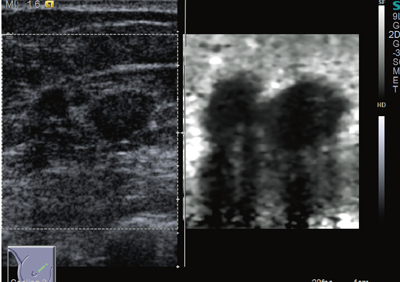

一般に,固体に衝撃を与えると弾性波が発生する。これには縦波と横波があり,それぞれ内部を伝搬する。このうち,横波である剪断弾性波に着目し,その伝搬速度(Vs[m/s])を測ることによって,組織の硬さを定量的に評価するのが,Virtual Touch Tissue Quantification(VTTQ)である。Vsの値が大きいほど,硬い組織であることを意味する。

VTTQでは,剪断弾性波を生体内の測定したい近傍で発生させる手段として,前述のARFIを用いる。収束超音波パルスが照射され,限局的に力の作用を受けた組織には,剪断歪みが生じる。力を取り除くと復元力が働き,組織は振動する。それが剪断弾性波となって,周囲に水平方向に伝搬する。これは,プローブでは感知できない方向であるため,小さなROIの内部を超音波断層法で高速スキャンを行い,組織の微細振動を検出して,剪断弾性波の伝搬速度を求める(図3,4)。

図4 Virtual Touch Tissue Quantificationの例(浸潤性乳管癌)

(画像ご提供:りんくう総合医療センター・位藤俊一先生)